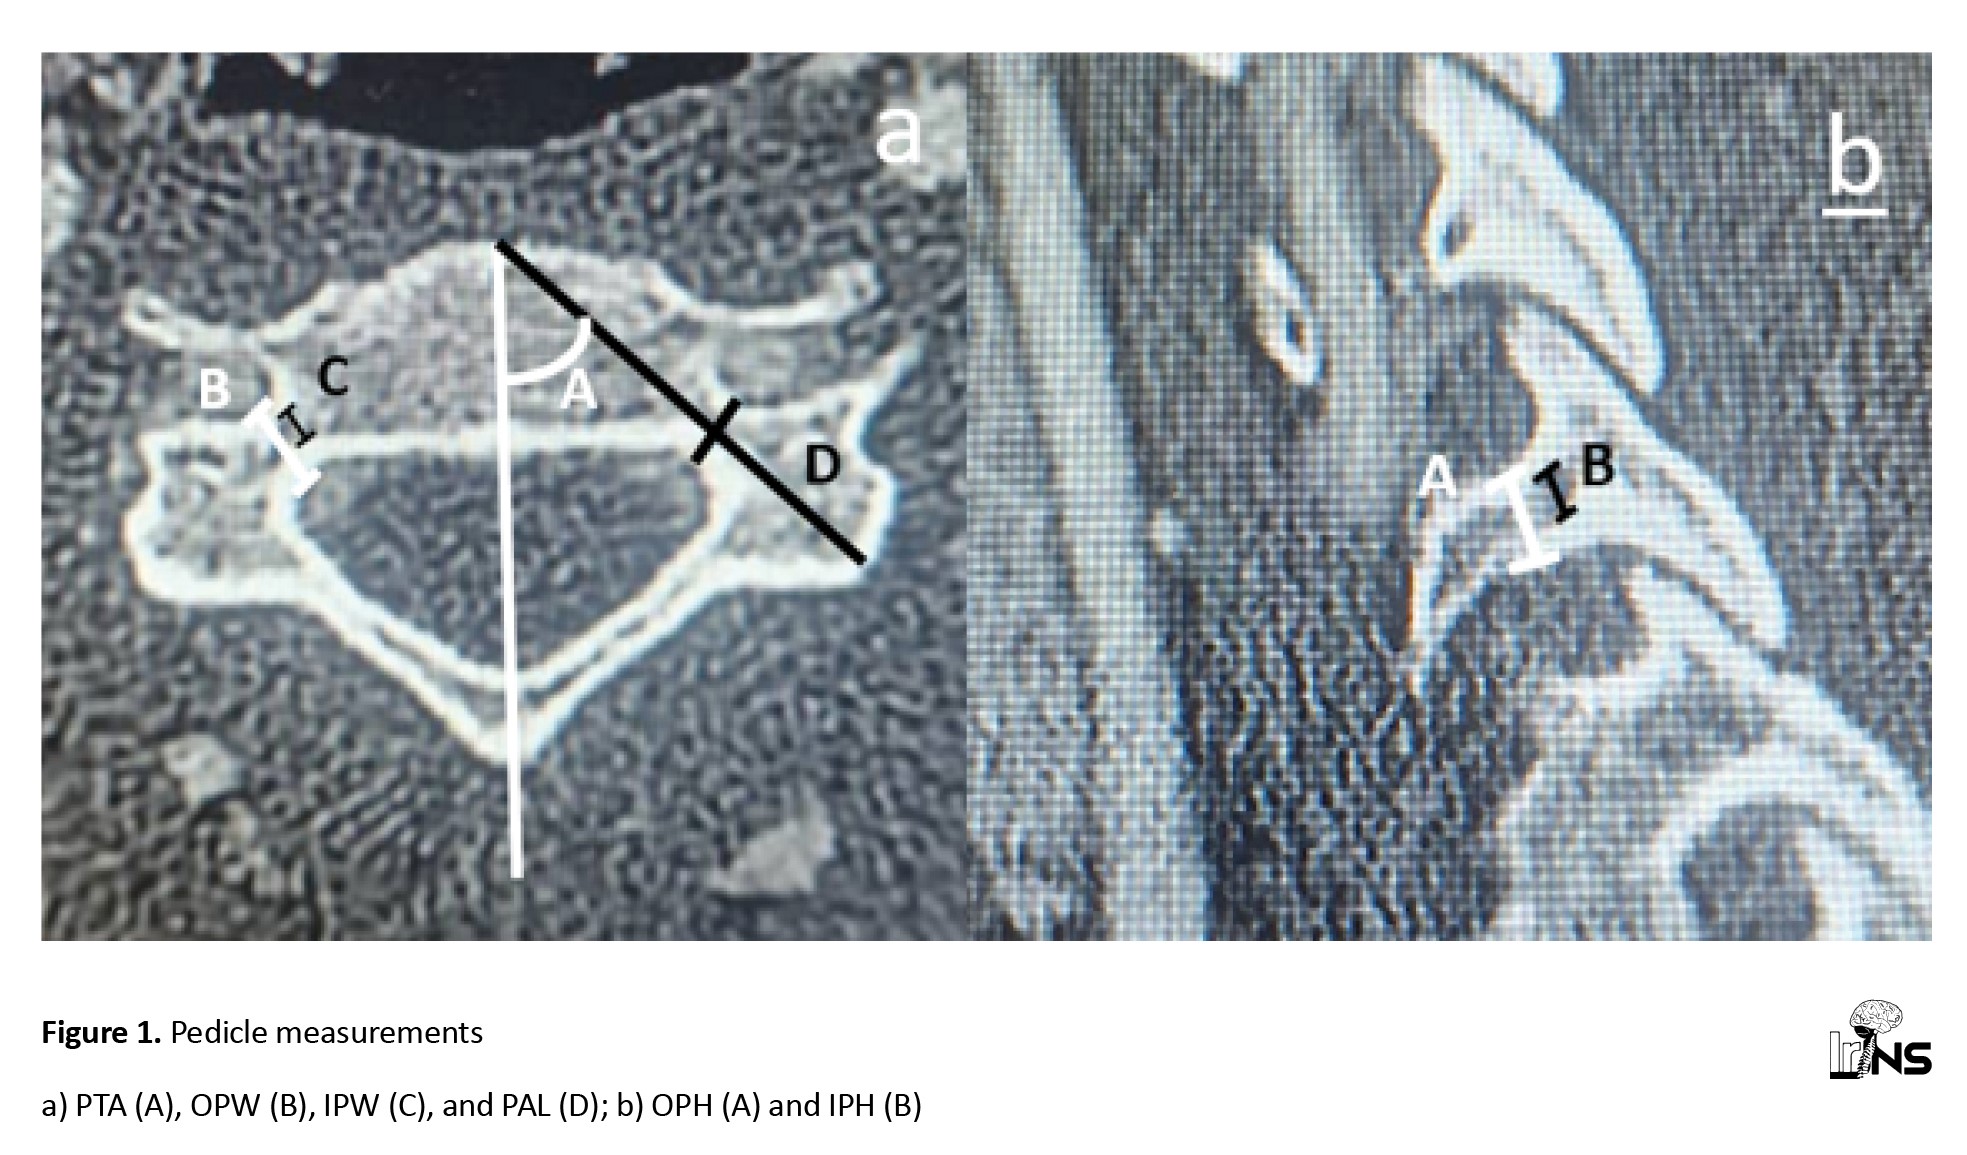

The parameters were measured on CT scan slices where their values were at their maximum, and the values were expressed in millimeters. The measured parameters are shown in the following figures (

Figures 1,

2, and

3).